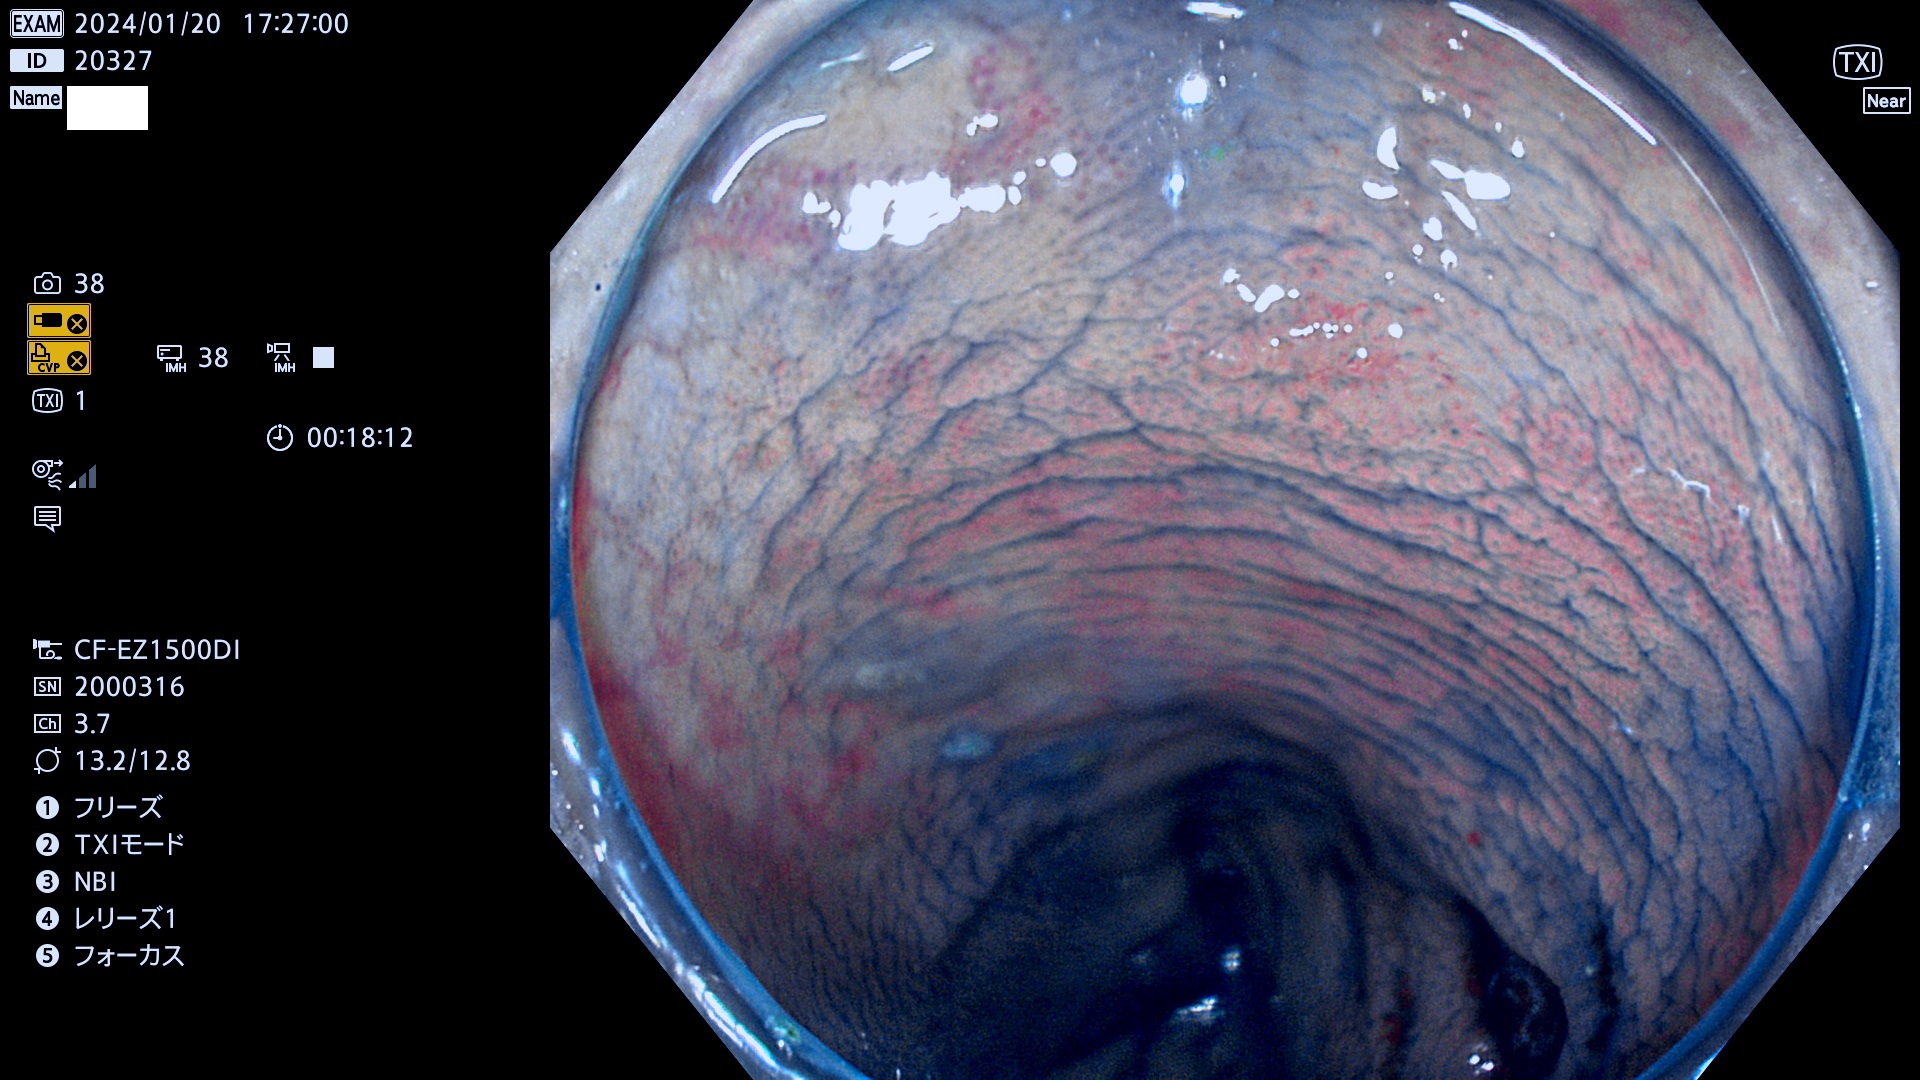

表面型腺腫(Flat Adenoma)の中で、完全に平坦な物をUb、陥凹している物をUcと呼びます。平坦隆起型(Ua)よりも、発見が難しく危険な病変です。

毎週の検査(木・金・土・日)に発見されたUb、Uc型・腺腫を、その週の日曜の夜にUPし1週間、提示します。

抽出の対象期間 2024年1月18日(木)〜1月22(月)の5日間(50件の検査)7件